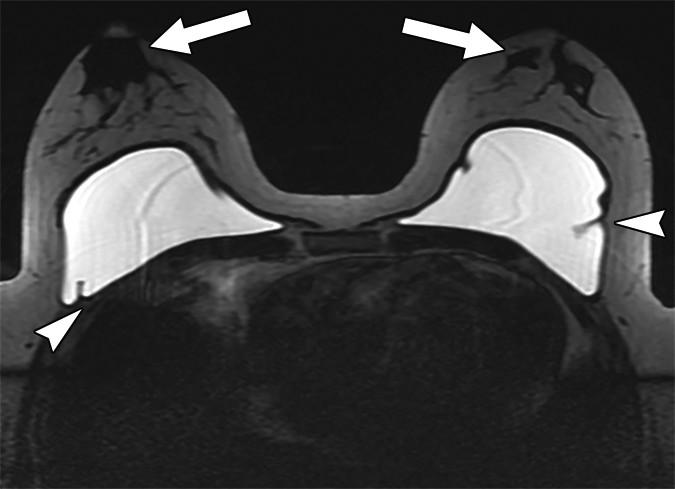

Related to gender affirmation surgery, silicone or saline breast implants in trans-females often evidence as incidental notations on chest radiography, CT, and MRI, yet the most common body contouring gender affirmation surgery is subcutaneous mastectomy. Since the nipple-areola complex is preserved, retaining malignant transformation risk, Doo et al. recommend trans-males submit to regular postsurgical breast cancer screening. Likewise, trans-female patients who have undergone neoadjuvant hormone replacement therapy have an increased risk for breast cancer and should be routinely screened.